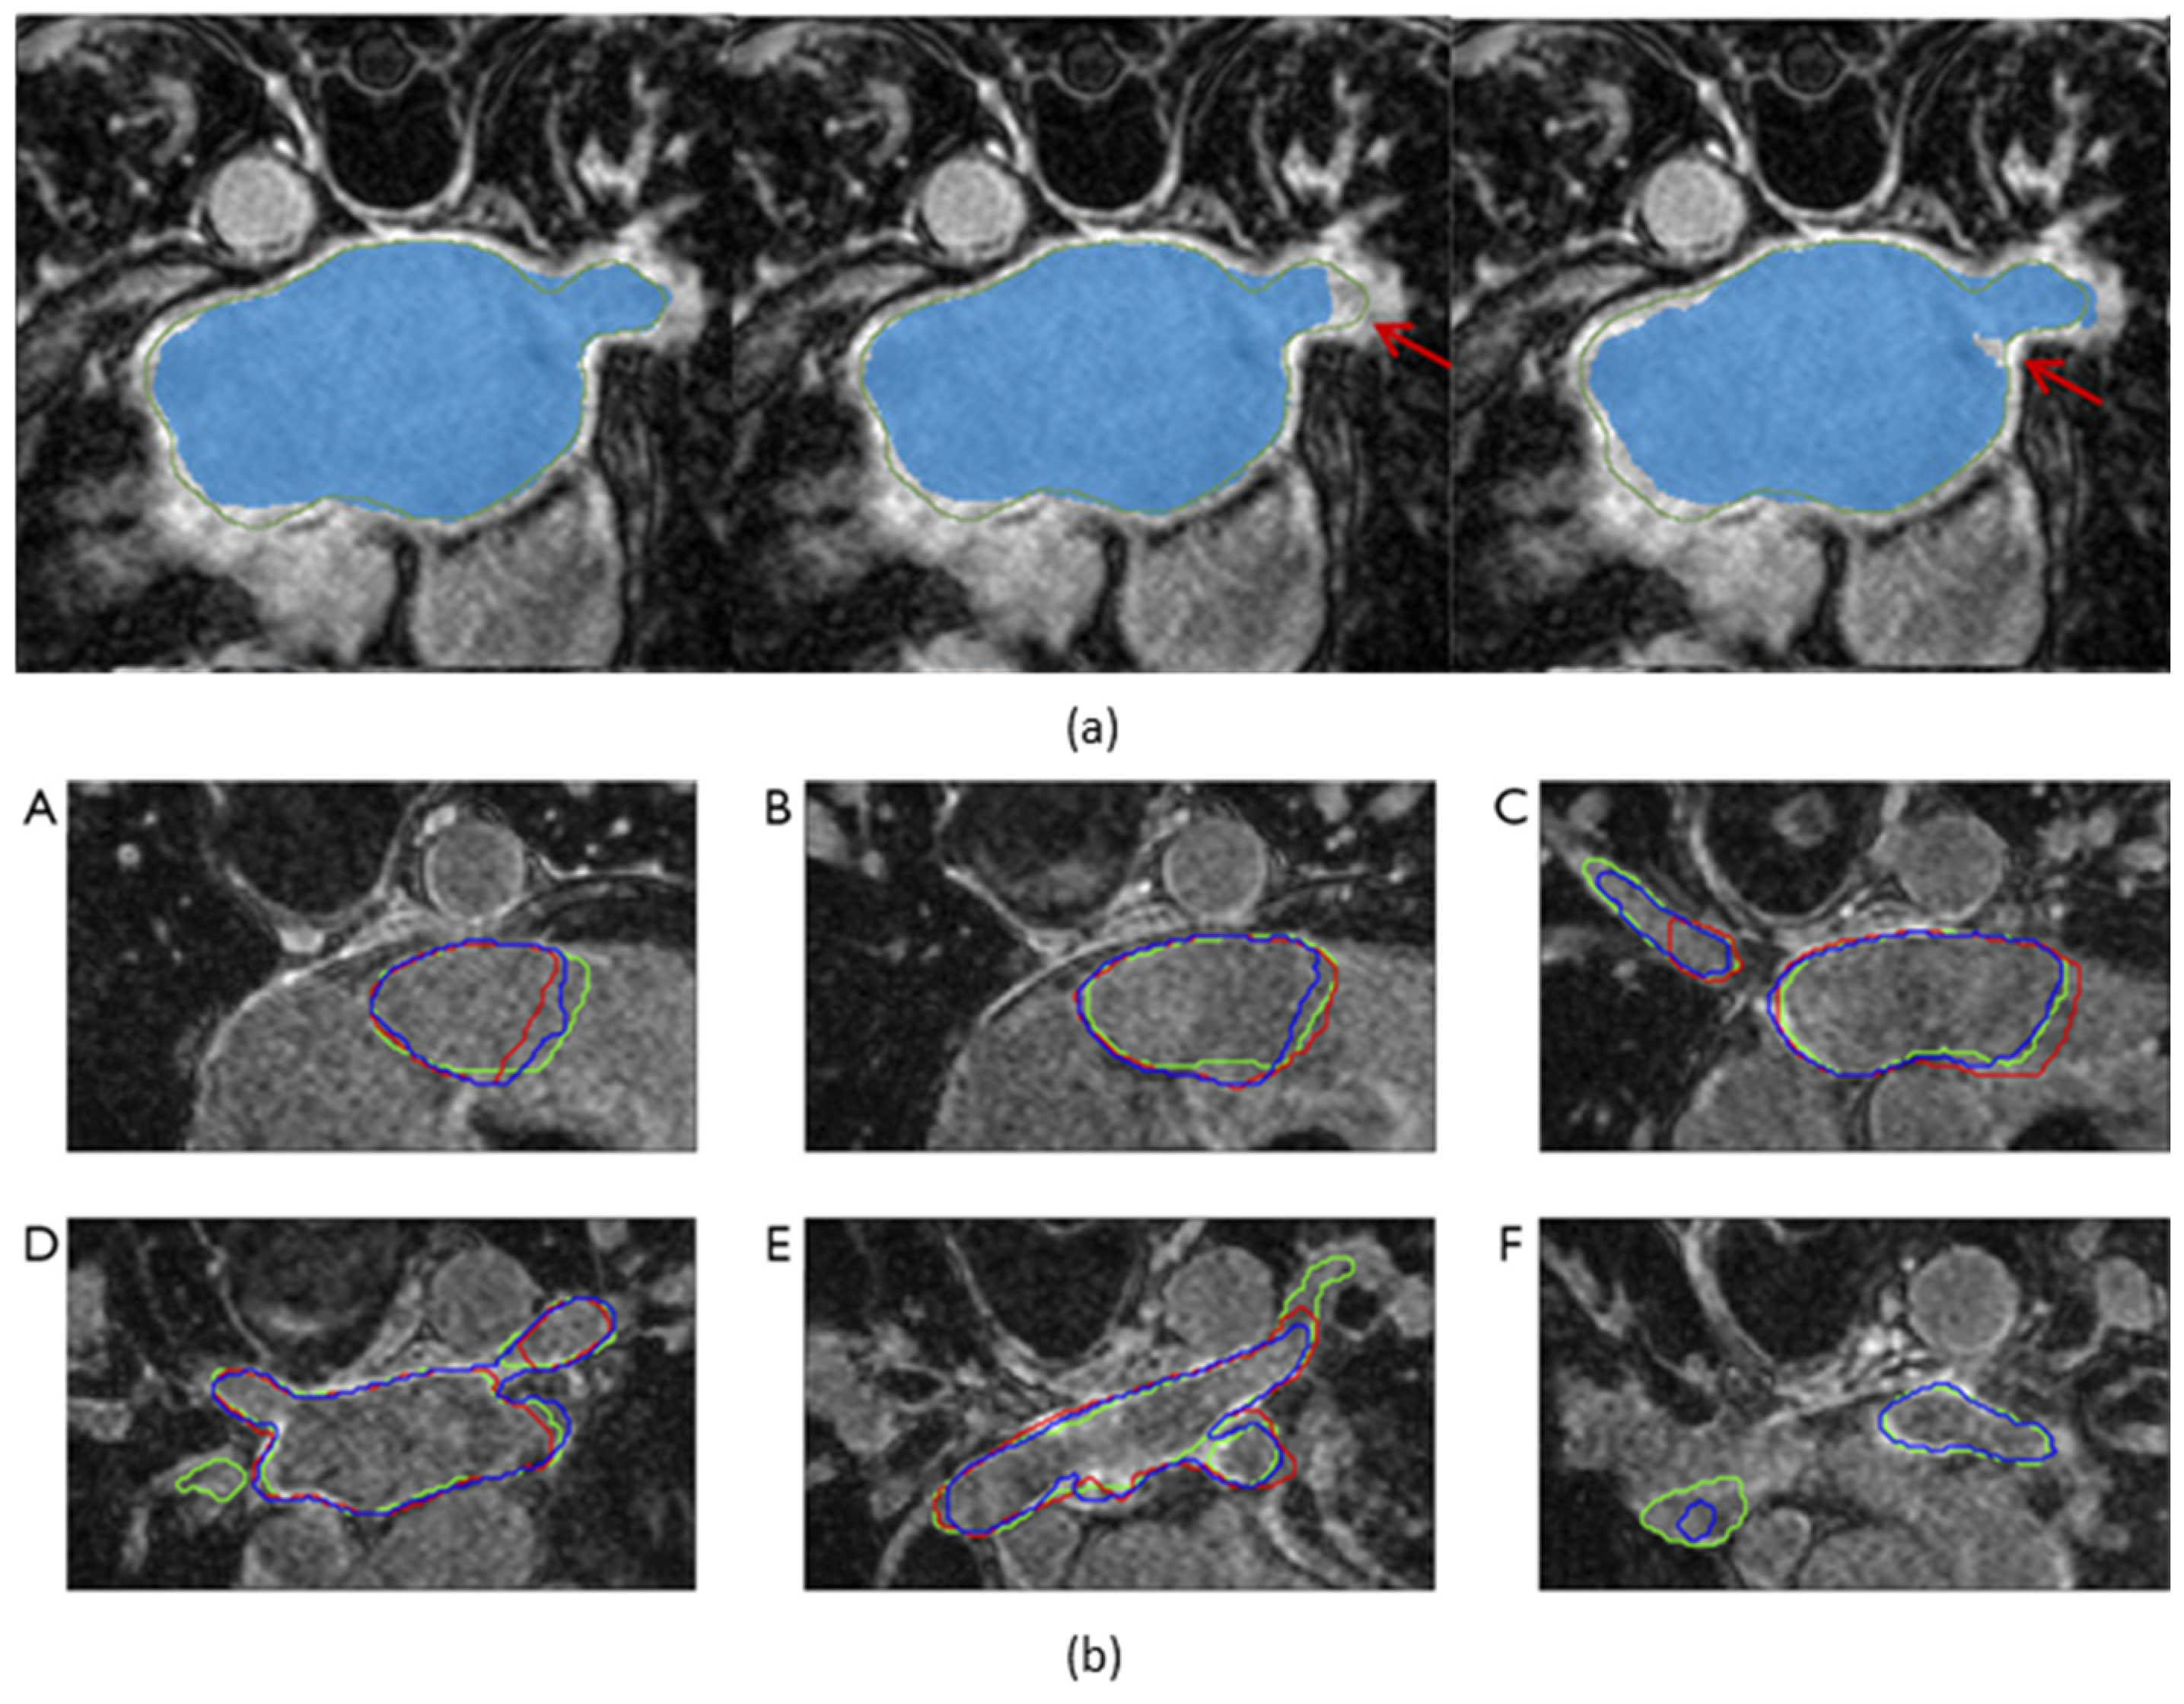

The impact of individual components of a proposed method can be evaluated by systematically removing these components and observing the impact on the model’s performance. Du et al. [25] enhanced its architecture by gradually introducing DPMs, MSCMs, GBMPMs, and a deep supervision mechanism, resulting in an improved DSC with each addition. Liu et al. [27] compared their proposed model with two other segmentation models. The first model had only an auxiliary supervision branch added to the decoder, while the second model had an SML structure but lacked an uncertainty-guided loss function. Their results indicated that incorporating an auxiliary supervision branch to the encoder improved both DSC and HD, while additionally including an uncertainty-guided loss function further improved the segmentation of the fuzzy surface of the LA, as illustrated in Figure 5a, leading to a reduction in HD.

Figure 5.

Visualization of the output segmentation maps superimposed on axial slices of late gadolinium-enhanced magnetic resonance imaging scans. (a) Comparison of the output segmentation maps. The green contours and the blue masks represent the ground truth and the model’s output segmentation maps, respectively. From left to right: the model with both the symmetric multilevel supervision (SML) structure and the uncertainty-guided loss function, the model with only the SML structure, and the model with only an auxiliary supervision branch added to the decoder. Red arrows point out disagreements between the model output and the ground truth. (b) This shows a decline in segmentation accuracy in the vicinity of the pulmonary veins. (A–F): axial slices 15%, 25%, 40%, 60%, 75%, and 85% along the longitudinal axis of the left atrium. The green, red, and blue contours represent the segmentation maps of the ground truth, 2-dimensional segmentation model, and 3-dimensional segmentation model, respectively. The 2-dimensional segmentation model completely failed on the slice 85% along the axis. Figure source: (a) [27], (b) [26].

While high performance in LA segmentation has been demonstrated by state-of-the-art segmentation models, suboptimal segmentation performance has been reported by multiple papers [17,25,26] in regions containing substructures of the LA. Specifically, Razeghi et al. [17] and Borra et al. [26] reported local segmentation performance in regions containing the PVs and the MV. Razeghi et al. [17] conducted 2D segmentation of the LA, MV, and PVs separately. While LA segmentation resulted in a DSC of 0.91 ± 0.02, which is consistent with the other state-of-the-art segmentation models, the segmentation of the PVs and the MV resulted in a DSC of 0.61 ± 0.08 and 0.73 ± 0.08, respectively, showing a decline in overall segmentation performance. Similarly, Borra et al. [26] examined the segmentation performance of the LA along its longitudinal axis, which was divided into three sub-volumes: adjacent to the MV, containing the LA body, and encompassing the PVs. While DSC remained relatively stable in the middle sub-volumes containing the LA body, a significant decrease was observed in the sub-volumes adjacent to the MV and encompassing the PVs. In these sub-volumes, 2D segmentation exhibited a greater decrease in performance compared to 3D segmentation, with a notably low DSC observed in the sub-volume containing the PVs, as shown in Figure 5b. Furthermore, Liu et al. [27] demonstrated that using V-net [41] resulted in high segmentation uncertainty in the regions with the PVs, while the addition of the SML structure as well as the uncertainty-guided loss function reduced the segmentation uncertainty. The PVs play a critical role in the onset of AF [12], but their shapes are highly complex and vary significantly between patients. In patients selected to receive catheter ablation, the most frequently practiced technique is PV isolation, which aims to electrically isolate the triggers in the PVs from the LA [8]. For the safety and effectiveness of PV isolation, it is crucial that the PVs can be segmented accurately. Future research should explore more accurate segmentation techniques to address the challenging shape of the PVs.